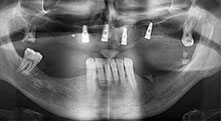

Bratu: Wir nutzen die Instrumente routinemäßig für die Entnahme von Knochenblöcken und das Spalten von Kieferkämmen. Weiterhin osteotomieren wir mit den Piezomed B6/B7 retinierte Zähne und entfernen nicht erhaltungsfähige Implantate. Alles Indikationen, bei denen es auf tiefe, saubere Schnitte ankommt.